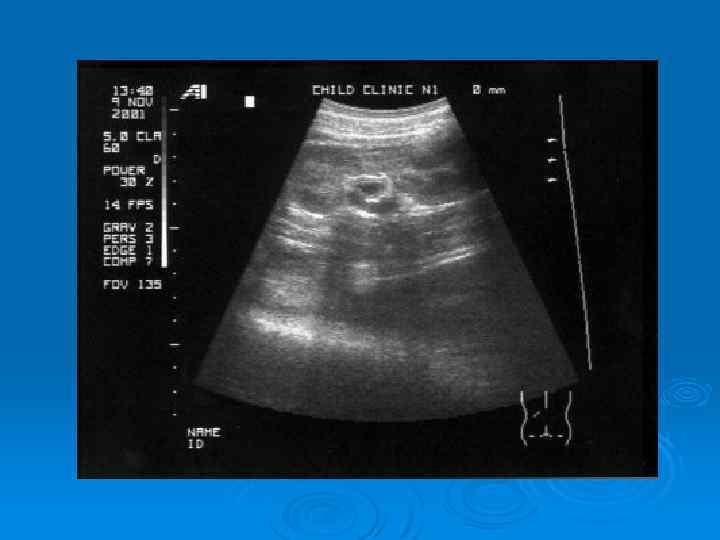

Утолщение стенки лоханки при остром пиелонефрите

Абсцесс верхнего полюса почки у ребенка, 11 лет